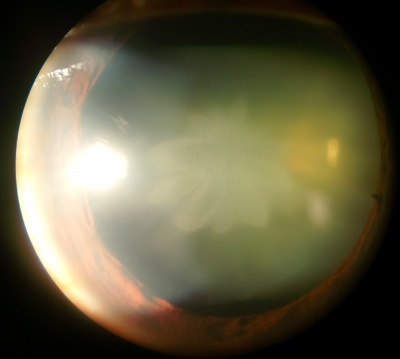

Nuclear Sclerotic Cataract

Etiology

Nuclear sclerosis is the yellowing and hardening of the central portion of the crystalline lens, and it occurs slowly over years. As the core of the lens hardens, it often causes the lens to increase the refractive power, leading to nearsightedness. This is why some patients who previously relied on reading glasses may no longer need them once a nuclear sclerotic cataract starts to form. This type of cataract can also cause colors to be less vibrant, although the change is so gradual that it is often not noticed.

Symptoms

- Blurring of distance more than near vision (typically, but others may notice worsening of reading more than distance)

- Increasing myopia ("second-sight" phenomenon of improved uncorrected distance vision in hyperopes and improved uncorrected near vision in emetropes)

- Poor vision in dark settings such as night driving

- Decreased contrast and decreased ability to discern colors

- Glare

- Monocular diplopia